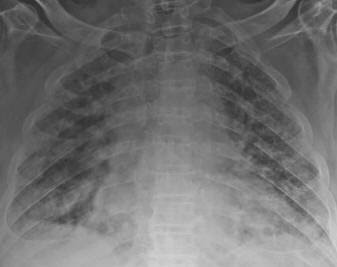

Radiografia del torace ( Rx torace). Permette di distinguere tra un edema polmonare interstiziale ed uno alveolare. La diagnosi si basa sulla clinica e sulla RX torace.

Una tipica radiografia del torace con edema polmonare può mostrare un aspetto più bianco su entrambi i campi polmonari.